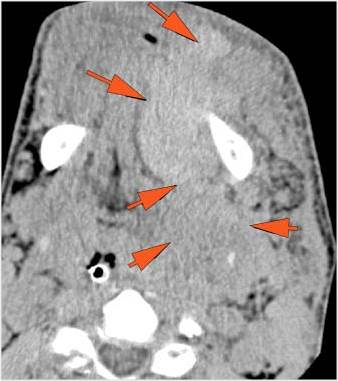

There is localized edema, hematoma or abscess within in the facial or scalp soft tissues, SMAS, infratemporal fossa, masticator space or oral cavity.

There is evidence of gas or a foreign body at a possible fracture site, indicative of an open or penetrating injury.

There is soft tissue swelling suggesting injury to the parotid or submandibular glands.